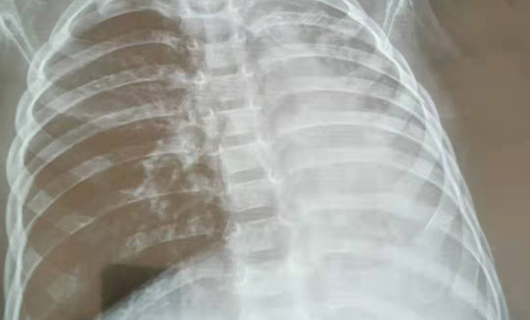

29个月的贝贝(化名)来院时发热2天,喘憋1天,脸色发紫。医生听诊发现,贝贝左肺几乎没有呼吸音,肺CT检查发现左肺完全不张。内镜下,边鹏确诊贝贝为塑型性支气管炎,左肺已堵满。

边鹏说,塑型性支气管炎发病急、死亡率极高,如治疗不及时,可致进行性呼吸困难,危及生命;或经治疗后症状好转,但遗留坏死性肺炎、闭塞性支气管炎等严重后遗症,给患儿肺功能造成不可逆的损害。支气管镜治疗是有效的处置方法。经多次吸引灌洗后清除塑型,镜下给药,贝贝终于平安了。